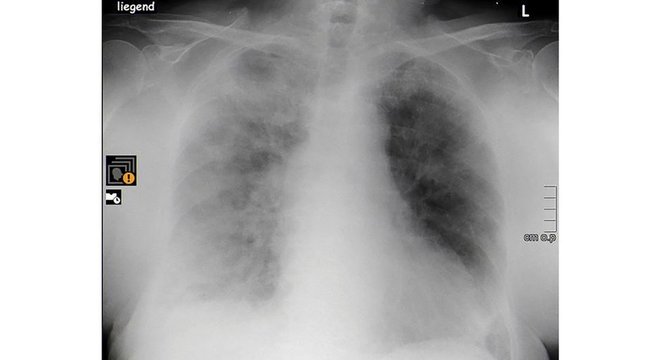

Raio X mostra pulmões de idosa de 84 anos, internada em hospital de Berlim, comprometidos pela covid-19

COURTESY OF HAVELHOEHE COMMUNITY HOSPITAL/HANDOUT